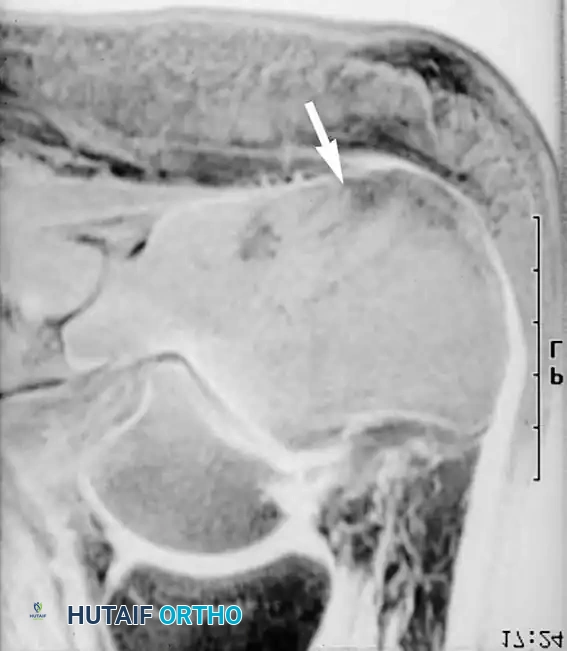

تشخيص آفات العظام ونخاع العظم

تلعب تسلسلات الرنين المغناطيسي المتقدمة دورا حاسما في التخطيط الجراحي من خلال تحديد الامتداد الدقيق للأمراض العظمية والغضروفية. بعض التسلسلات التي تقوم بقمع إشارة الدهون تكون حساسة للغاية، حيث يمكنها إظهار ارتشاح ونزيف نخاع العظم التفاعلي قبل وقت طويل من حدوث انهيار هيكلي في العظم.

هذه المبادئ التصويرية تنطبق على الطرف السفلي بأكمله. على سبيل المثال، حالات التهاب العظم والغضروف السالخ أو التهابات العظام في القدم والكاحل تظهر بوضوح عبر هذه التقنيات.

علاج عيوب الغضروف المفصلي والعظام

في حالات التهاب العظم والغضروف السالخ، يتدخل الجراح عندما يظهر الرنين المغناطيسي وجود سوائل خلف القطعة العظمية مما يدل على عدم استقرارها. تتراوح الخيارات الجراحية بين التثقيب بالمنظار لتحفيز النخاع العظمي على الشفاء، إلى تثبيت القطعة المنفصلة، أو زراعة غضروف ذاتي في حالات العيوب الكبيرة.